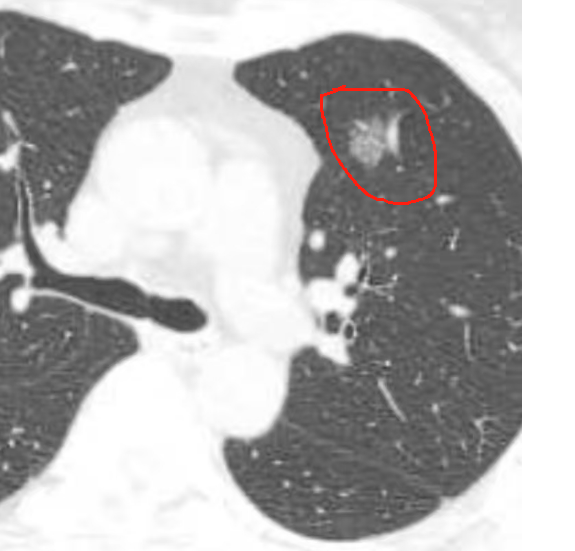

患者是一名 60 岁女性,在外院胸部 CT 检查发现左肺上叶前段不规则磨玻璃结节,考虑为早期肺腺癌,经人介绍后来到桂医二附院胸心血管外科,找到了吴云飞博士。患者畏惧手术,对手术疼痛感到极度担忧,担心手术切除肺后出现肺功能显著下降,生活质量影响大......

吴云飞博士表示,精准肺段切除术的难点在于每一个患者都存在独有的解剖结构,肺段解剖变异性非常大。左肺上叶前段的血管、支气管分布存在较多变异,且与周围肺段的解剖关系紧密。术中需精准识别靶段的动静脉、支气管,避免误断或漏断,否则可能导致术后出血、漏气或肺功能受损。